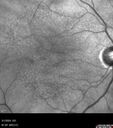

84 year old female The patient had cardiac stents done a week ago. Her stent was done late in the day. She did not notice anything that night but the next morning she noticed that it looked like there was steam coming out of the vent in the ceiling and like there was moister on the mirror. After that her vision changed to look like there was smoke inside her eye. This is more on the left eye than the right eye. Medical Hx: Influenza Immunization Not Received. Pneumococcal Vaccine Not Received. Diabetes Mellitus. Heart attack (2/23/2024). Hypertension, Systemic. Hyperlipidemia. Surgical Hx: Heart Stent (2/23/2024). Hysterectomy. Systemic Meds: Aspirin 81 mg. linaglitin. Metoprolol. NITROGLYCERIN. Ticagrelor. VALSARTAN. VA OD: Dcc20/32 Ncc20/200 VA OS: NccJ16 IOP: TP: OD:11 OS:10

Reticular pseudodrusen85 views00000